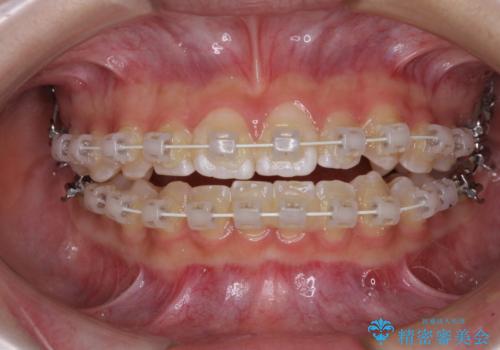

- 審美装置

- 1年2ヶ月

左右ともに上顎第二大臼歯が外側に転位しており、大変磨きにくくなっているため、補助装置により内側に引き込むことで改善することとしました。

外側を向いていた奥歯は比較的早い時期に歯列に収まり、咬み合わせも磨きやすさも改善することができました。